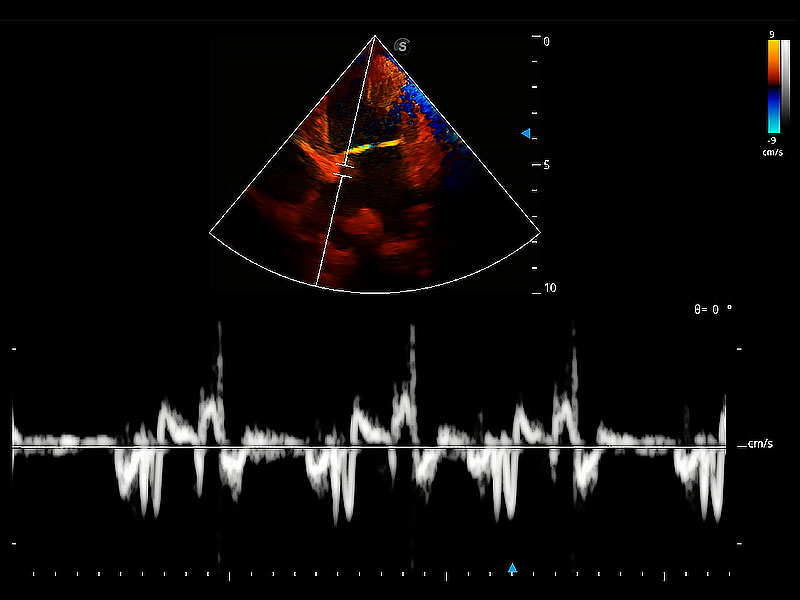

實(shí)時(shí)用顏色表示心肌組織運(yùn)動(dòng),觀察和定量組織的運(yùn)動(dòng)情況,對(duì)快速檢測(cè)與評(píng)估心肌的灌注和活性、電傳導(dǎo)及心肌收縮和舒張功能等均能提供重要的診斷信息。

ProPet 80 配備了豐富的心臟探頭群、先進(jìn)的成像技術(shù)和專業(yè)的心臟測(cè)量工具,可幫助動(dòng)物醫(yī)生為不同體型和生理結(jié)構(gòu)的動(dòng)物提供心臟和心肌功能的全面評(píng)估。

隨著取樣門位置改變,頻譜多普勒包絡(luò)可進(jìn)行自動(dòng)眼蹤測(cè)量,且可自由配置測(cè)量的參數(shù)。